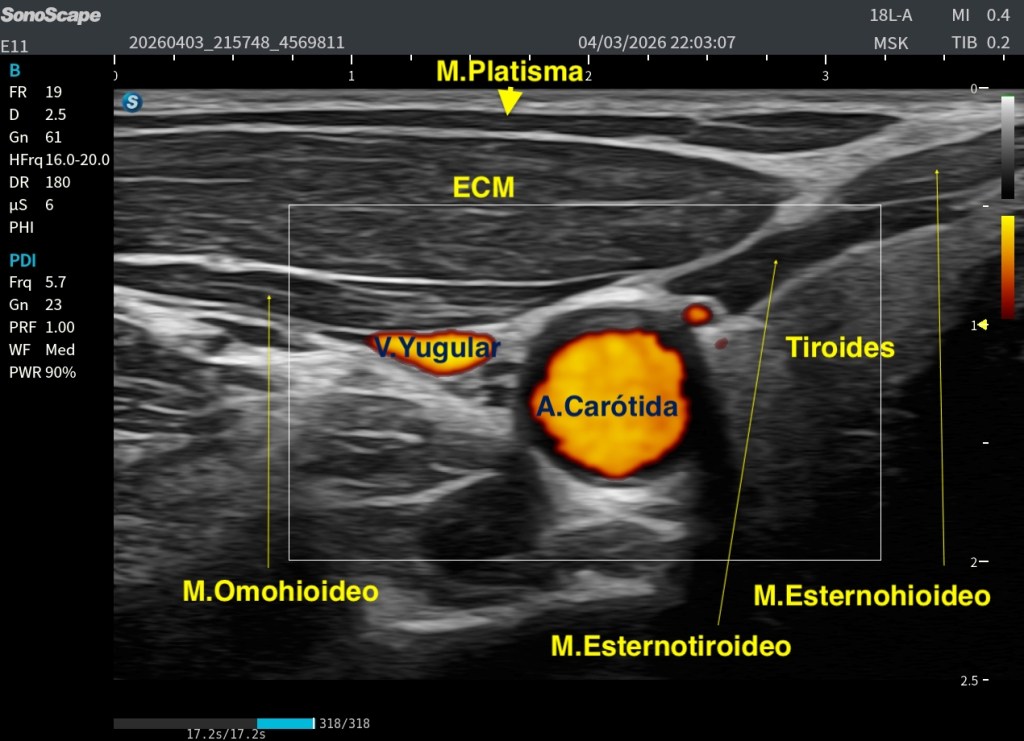

El Platisma es un músculo superficial, plano y muy fino, situado justo por debajo de la piel y del tejido celular subcutáneo, es el músculo más superficial del cuello.

Por encima de él solo encontramos piel y grasa, tejido celular subcutáneo en más o menos medida. Por debajo, ya entramos en estructuras más profundas del cuello anterior.

Ahí es donde empiezan a aparecer músculos como:

- El Esternocleidomastoideo ECM

- Los músculos infrahioideos (Omohioideo, Esternohioideo, Esternotiroideo)

- Glándula tiroidea

- Y más profundo aún, el paquete vascular con la carótida y la yugular

Por eso, el Platisma tiene una importancia clave: Marca el límite entre lo superficial y lo profundo en el cuello.